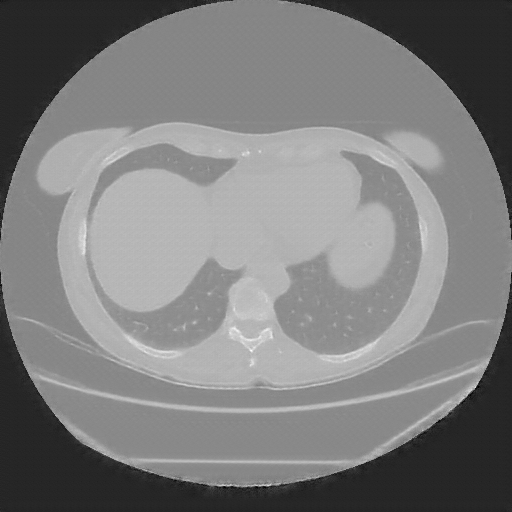

Original NATIVE CT scan (input)

No window - Raw intensity values

Lung window (WL -600, WW 1500 β†’ Low βˆ’1350, High +150)

Mediastinum window (WL 40, WW 400 β†’ Low βˆ’160, High +240)